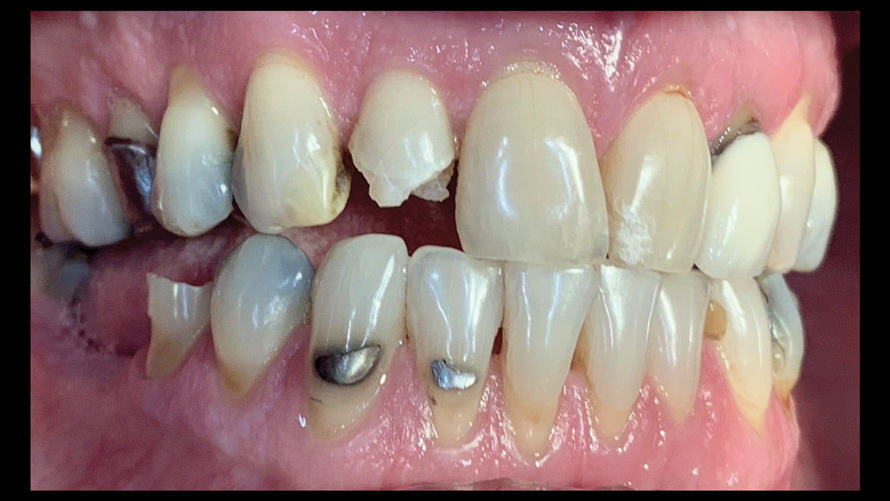

(9.) Preoperative esthetic case documentation using a smartphone and an EALS device.

Figure 9

(10.) Preoperative esthetic case documentation using a smartphone and an EALS device.

Figure 10

(11.) Preoperative esthetic case documentation using a smartphone and an EALS device.

Figure 11

One of the main advantages that smartphone cameras have over DSLR cameras is that nearly everyone is already very familiar with the technology; therefore, the incorporation of these devices into everyday practice does not require learning a new and unfamiliar skill set. The task of producing a series of high-quality clinical photographs for routine examinations (Figure 8), esthetic treatment planning (Figure 9 through Figure 11), or specialty care (Figure 12 and Figure 13) can be delegated with confidence to any staff member during the patient's initial office visit and will generally require less than 5 minutes of time to complete. When a DSLR camera is used, evaluation of the intraoral images either takes place on the small viewfinder built into the camera or necessitates the physical removal of the memory card from the camera to downloaded the images onto a computer for review. An added bonus of smartphone dental photography is that the phone's screen now replaces the much smaller viewfinder of a DSLR camera and provides the clinician with the ability to view and zoom into the patient images on a 5- to 6-inch, high-definition display.